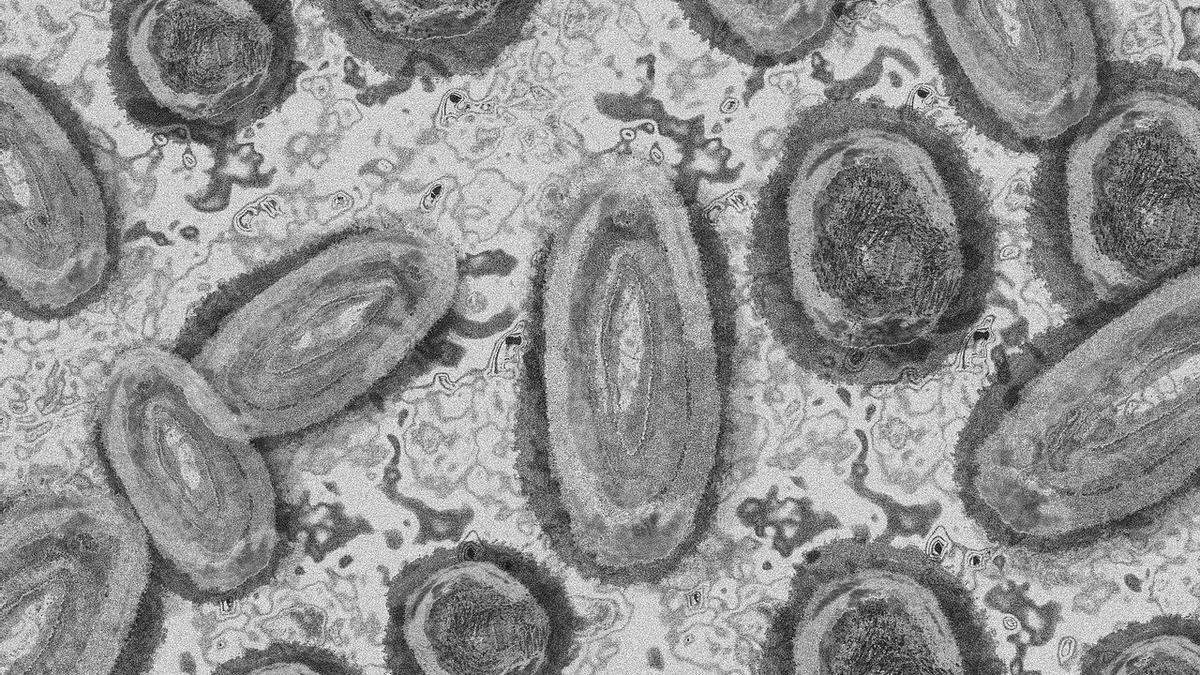

La viruela del mono es una enfermedad endémica del continente africano, donde varios mamíferos pueden transmitirla al ser humano. Causa erupciones en la piel. Según la OMS, causa una letalidad del 1% al 10%, especialmente entre la población infantil.

Esta enfermedad, causada por un virus de viruela transmitido de los animales a los humanos, se contagia por contacto con una persona infectada o con sus fluidos corporales, incluida la saliva. Sin embargo, según la agencia británica de seguridad sanitaria (UKHSA), el virus no se contagia "fácilmente" entre personas por lo que el riesgo para la población es "bajo".